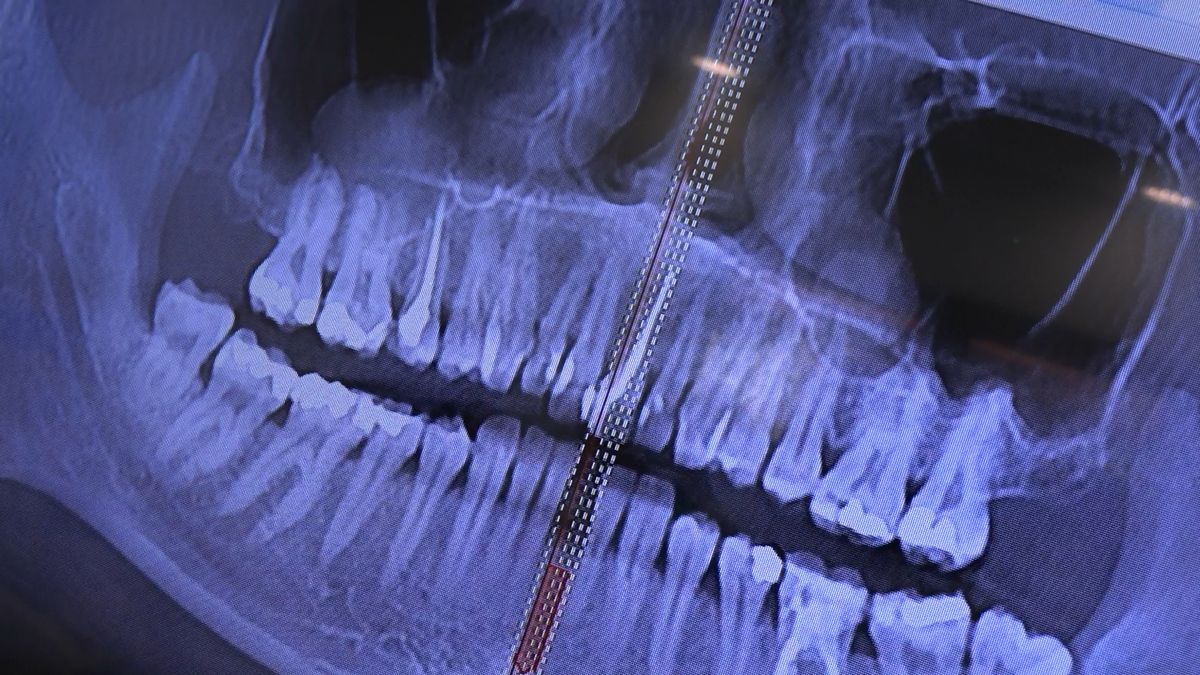

Practiculum Implantologii – Sezon VIIB, sesja 7, dzień 2